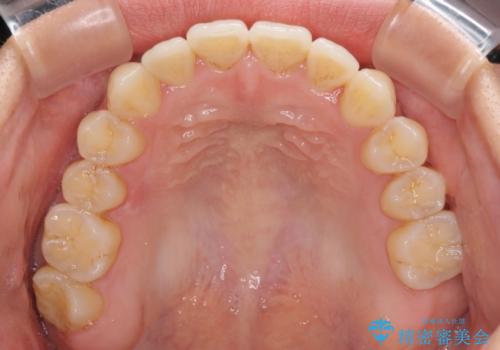

前歯のデコボコ インビザラインによる矯正治療

- 上下前歯の叢生と奥歯の反対咬合を気にして来院された患者様です。

インビザラインを用い、下顎はIPR(歯と歯の間を削る)と歯列全体を後方に移動させ、上顎は側方に拡大させることで歯列を改善していくこととしました。

骨格的に下顎が左側前方にずれているため、上下正中のズレや左右奥歯の咬み合わせを理想的な状態とすることは困難でした。